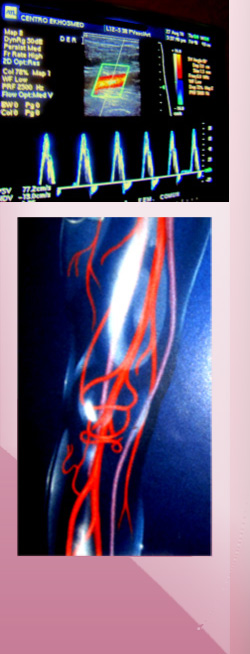

La ecografía Doppler color muestra velocidad y orientación del flujo de sangre en las arterias, permitiéndonos ver áreas oclusión arterial (cierre) o de disminución del flujo sanguíneo por reducción parcial del lumen vascular.

Contamos con equipos de ecografía Doppler color de alta resolución.